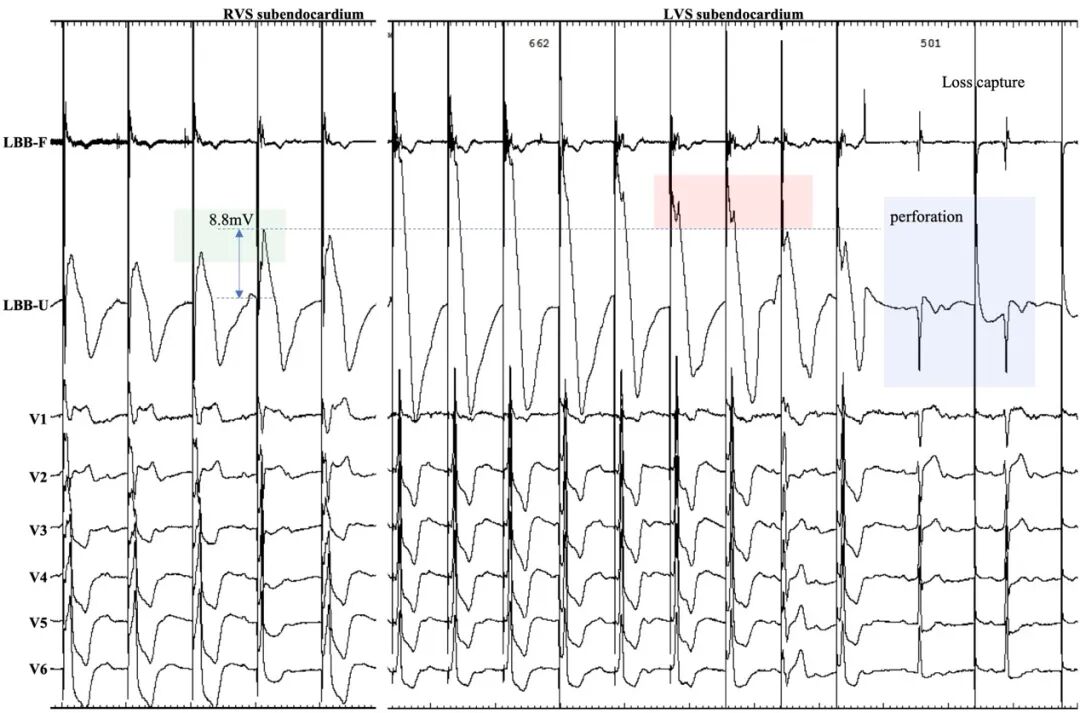

4.实时ECG/EGM监测提供室间隔内电极位置信息反馈(图3):

在手术中持续记录12导联ECG和EGM,通过动态分析QRS波形态、刺激到V6波峰时间(Stim-V6RWPT)等参数,实时反馈导线位置及是否精准夺获LBB。

将3830起搏电极tip端单极连接江氏线,在2V/0.5ms连续起搏下拧入电极,过程中失夺时,则升高起搏电压,以最低输出夺获下拧入电极。损伤电流(COI)持续升高为电极有效拧入标志,此阶段可快速拧入。在右侧间隔起搏到深间隔起搏中COI为持续上升过程,直到首个左侧间隔起搏模式出现时COI最高,之后则为逐渐下降。出现左侧间隔起搏模式后,增加测阻抗频次,重点关注相邻两跳ECG形态与Stim-V6RWPT的差异。当高-低输出存在Stim-V6RWPT跳短或ECG形态变化(如V6新现S波/或原有S波加深等现象)时,需进一步放缓拧入速度。当标测输出发生相邻两跳ECG形态骤然变化伴或不伴Stim-V6RWPT缩短时,均需暂停拧入,降输出以观察S-V分离与否。S-V分离未现时, 在COI许可情况下(>5mV),以最低夺获输出下谨慎拧入,直至分离(图4)。穿孔提示:通过监测COI的实时变化,当导线过深时,COI信号出现突然降低/消失,可能提示间隔穿孔,需立即停止操作(图5)。

图4.通过实时监测ECG和EGM变化确定起搏电极位置并识别左束支夺获。

图5.对照右侧间隔COI变化推测左侧COI振幅,实时监测穿孔发生。